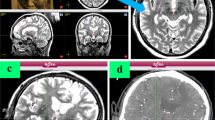

All patients received a preoperative T1 MRI with gadolinium and a T2 MRI using a GE LX, 60-cm bore, 1.5 Tesla MRI under general anesthesia (Fig. 1a) (1 mm slice, matrix 512 × 512, 0.487 × 0.487 mm in-plane resolution). The MRI was calibrated using the American College of Radiology standard phantom tests.2 For the first twelve patients, the MRI and the electrode placement procedure were performed on the same day and under the same anesthetic; however, following a practice change, the MRI and trajectory planning were performed under general anesthesia the day prior to surgery for the remaining patients. On the day of surgery, the patient is positioned using a head clamp (Doro 4002-20, Pro Med Instruments, Freiburg, Germany) customized for use with intraoperative CT, which would not be necessary for an awake DBS procedure. The surgical plan is verified and measurements are taken for the placement of the Renaissance robot (Mazor Robotics, Caesarea, Israel) attachment base. High precision of the robot base in not required as long as the robot is attached on the skull in a location where the robot can reach the target trajectories. The robotic software calculates a series of possible mounting locations. Calipers are used to triangulate from known anatomic landmarks or fiducial markers to the selected base location. A sterile field is then created and a fiducial frame, known as the Star Marker, is attached to the base that allows the planning software to orient the Renaissance system to the patient and intraoperative CT scan (Fig. 2a). The intraoperative CT (2 s. rotation, 120kv, 7 mA, 1.25 mm slice thickness, 0.494 × 0.494 mm in-plane resolution; CereTom™, Neurologica Corp., Danvers, MA.) is obtained in a sterile fashion (Fig. 1b) and then fused with the preoperative MRI (Fig. 1). When the CT is fused to the MRI, the robot base location is known relative to the target trajectories. This intraoperative CT is referred to in this study as the fiducial CT. The MRI-CT fusion process is completed in the Mazor Renaissance software. It involves an initial manual alignment performed by the surgeon, followed by the software registration algorithm completing the six-degree-of-freedom fusion. Once completed, the fusion is visually inspected by the surgeon for success.

(a) Preoperative T2 MRI acquired with a 1.5 Tesla machine under general anesthesia (top), with preoperative cannula trajectory plan for the right STN shown in blue (bottom). (b) Intraoperative CT (including fiducial frame for orientation of the renaissance system). (c) Fusion of MR and CT scans; transparent overlay of T2 MRI and intraoperative CT (top), intraoperative CT with T2 MRI shown within window (bottom). (d) Intraoperative CT with preoperative plan mapped from the fused MRI shown in blue. Sagittal and axial images that pass through the right STN are shown in each instance.